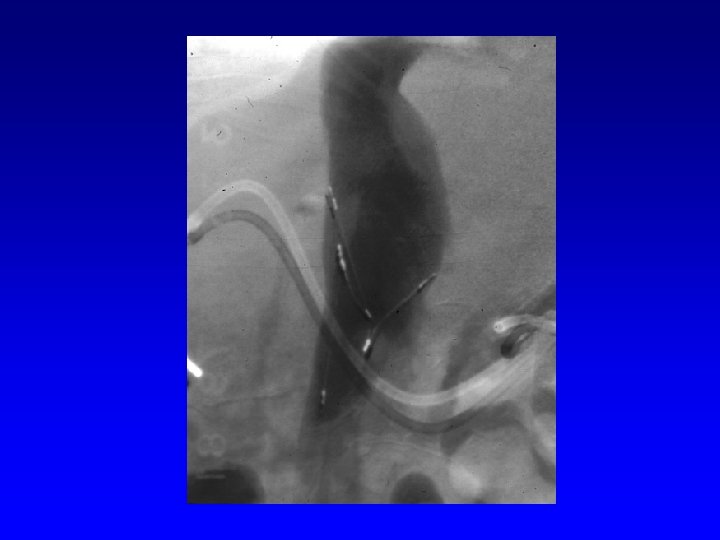

Retrieval with a snare and a long sheath or guiding catheter Günther Tulip (Cook) Celect (Cook) Opt Ease (Cordis Endovascular) Option (Angiotech) G 2 X, Eclipse, Meridian (Bard)

Snare Retrieval En. Snare